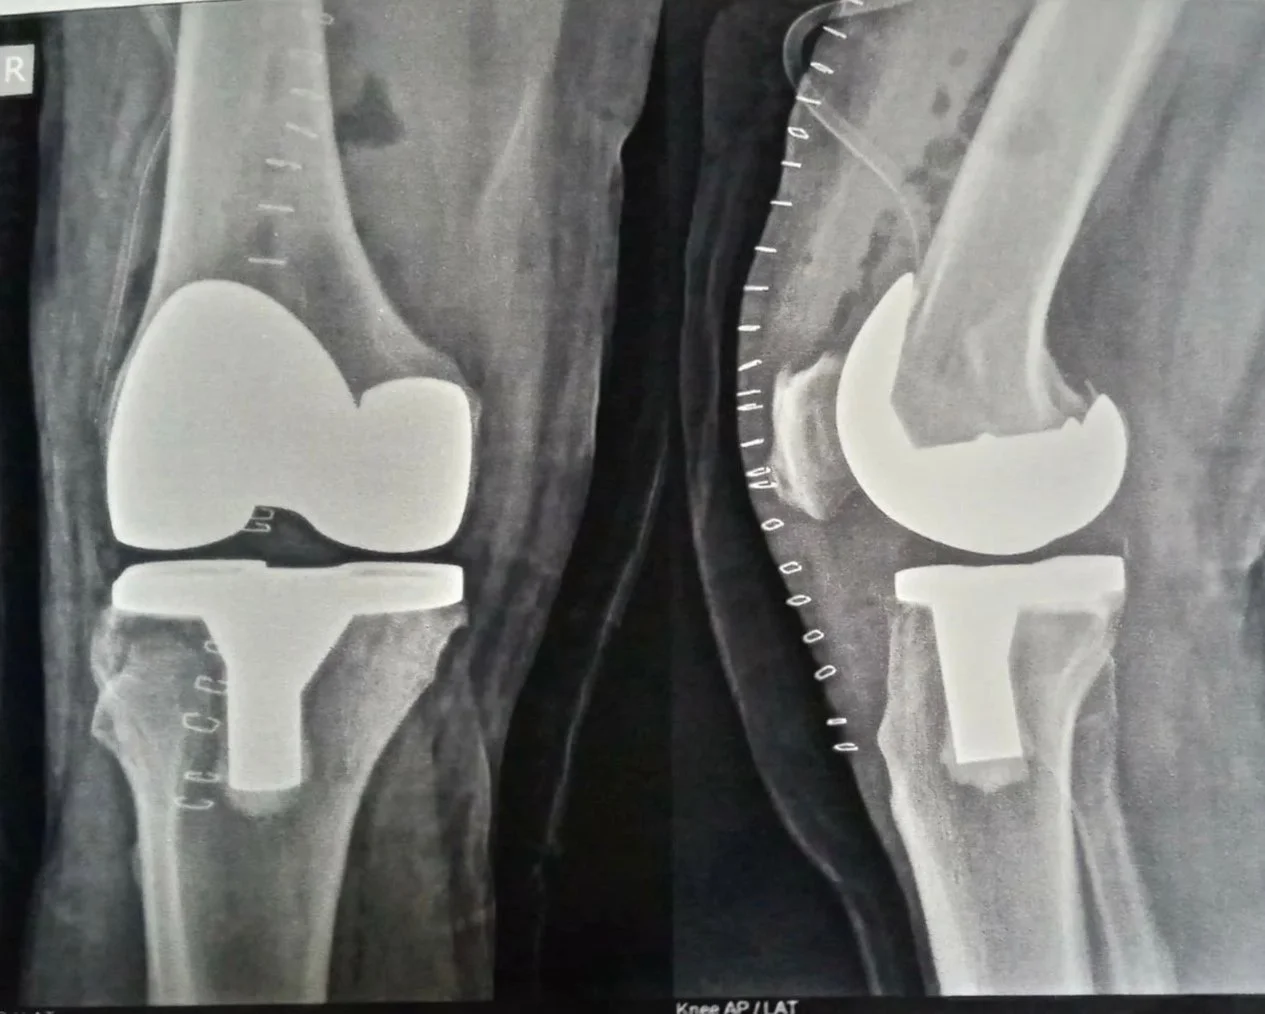

Total Knee Replacement

Chronic knee pain from arthritis or injury can be life-limiting. Total knee replacement restores mobility, eliminates pain, and gets you back to daily activities — typically within 6–8 weeks of surgery.